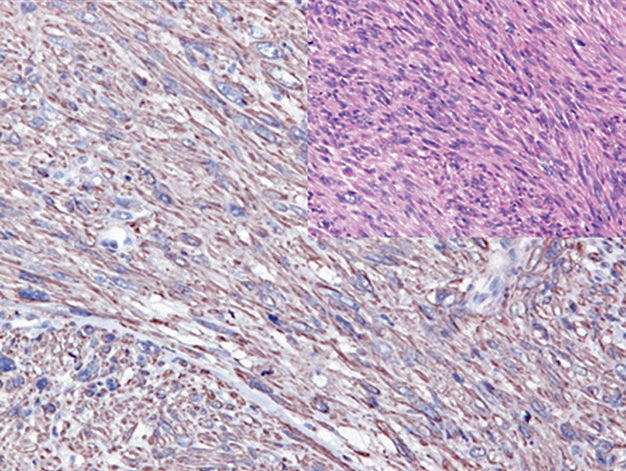

图3. 胚胎性横纹肌肉瘤中,EGFR强阳性表达。